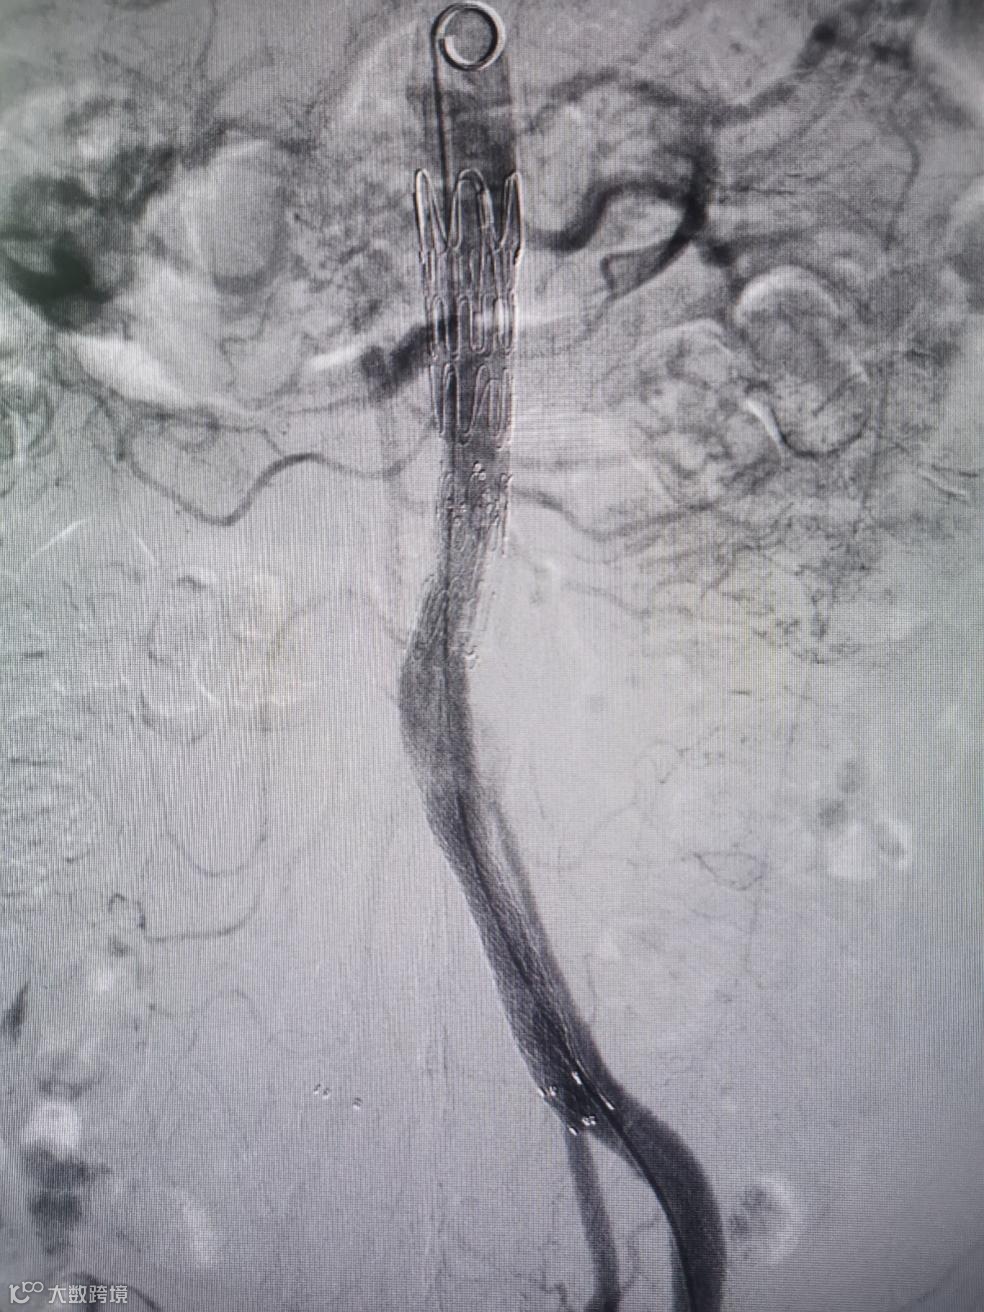

Separator With Aspiration catheter for Mechanical Thrombectomy(MT)【分离器辅助导管抽吸技术】:旨在提高整体系统的抽吸效率和治疗安全性,快速帮助血栓清除。

1)抽吸导管头端堵管,分离器可以快速疏通导管,降低撤管冲洗的频率。

2)针对大负荷血栓或亚急性血栓,分离器辅助下抽吸能提升整体系统抽吸效率,缩短手术时间。

手术过程